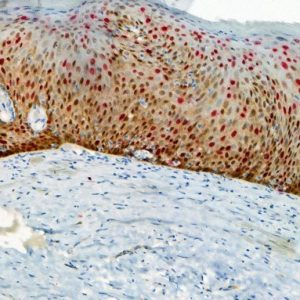

Isocitrate dehydrogenase 1 (IDH1) is an enzyme that catalyzes the oxidative decarboxylation of isocitrate to alpha-ketoglutarate, producing NADPH (1). However, abnormal IDH1 caused by somatic missense mutations may occur when substitution from arginine to histidine at codon 132 (IDH1 R132H) inhibits the wild-type IDH1 enzymatic activity, leading to production of 2-hydroxyglutarate, a possible oncometabolite. The accumulated oncometabolite promotes formation and malignant progression of gliomas (2). IDH1 R132H detection by immunohistochemistry can be used for the diagnostic differentiation between grade II/III gliomas, secondary glioblastomas and primary glioblastomas. The IDH1 R132H mutation correlates with a positive clinical outcome in patients with astrocytic tumors. Recently, studies indicated that IDH mutations along with ATRX status, and in combination with other classical biomarkers, helped refine the molecular classification of adult gliomas, providing a prognostic tool for clinicians (3). Data indicate that IDH1 R132H expression could be used as a predictive marker of prognosis for patients with gastrointestinal cancer (1).

| CLONE | IHC132 |

| POSITIVE CONTROL | Astrocytoma |